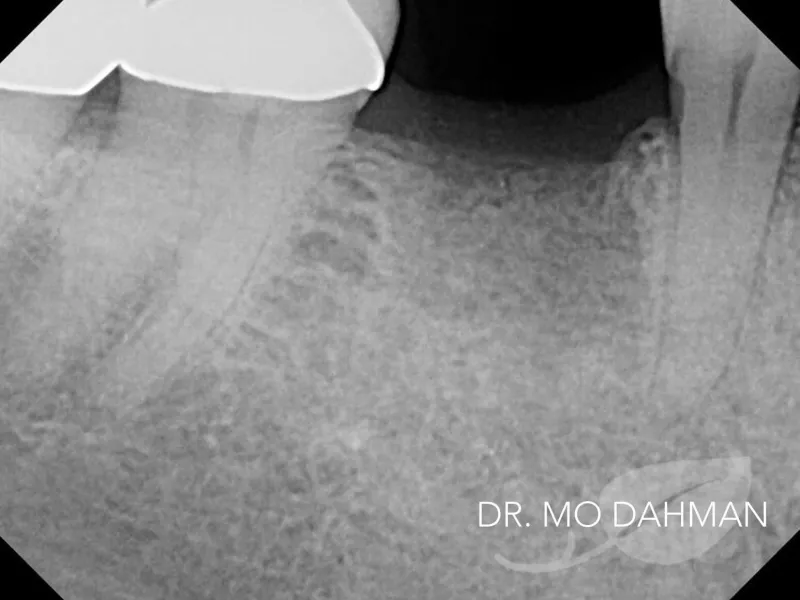

This patient had an old root canal received from a prior dentist that was failing. It was extremely painful.

It was immediately apparent the tooth was no longer salvageable and the proper route was to extract and replace the tooth with a new dental implant.